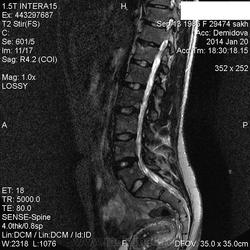

Вторая пациентка:

В телах позвонков определяются множественные очаги и фокусы разной степени интенсивности понижения МР-сигнала по Т1, Т2 ( первые 2 картинки), неоднородного повышения по Т2 с жироподавлением ( третьи картинки).

Контрастирование  не проводили.